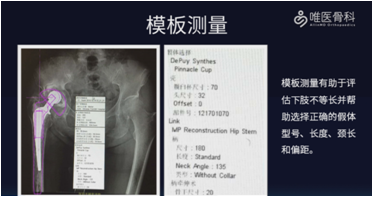

完善常规术前检查,排除手术禁忌。同时结合影像学资料,评估骨缺损的类型以及假体松动的情况,并进行详细的模板测量,评估下肢长度,并帮助选择正确的假体型号、长度、颈长和偏距。此外,还需准备好假体及骨水泥取出器械,准备扩大转子截骨(ETO)所需的器械及钢丝捆绑带等。

骨缺损的处理和水泥假体的取出一直是THA翻修术所面临的主要挑战,不仅需要处理严重丢失的骨量,亦需要恢复关节的正常力线和稳定。因此,术前我们应该充分评估骨缺损的类型,制定合理的重建方案。并通过详细的模板测量,初步预判假体的型号和大小。尤为关键的是,假体和骨水泥专用取出工具的使用是确保手术顺利进行的有力保障。